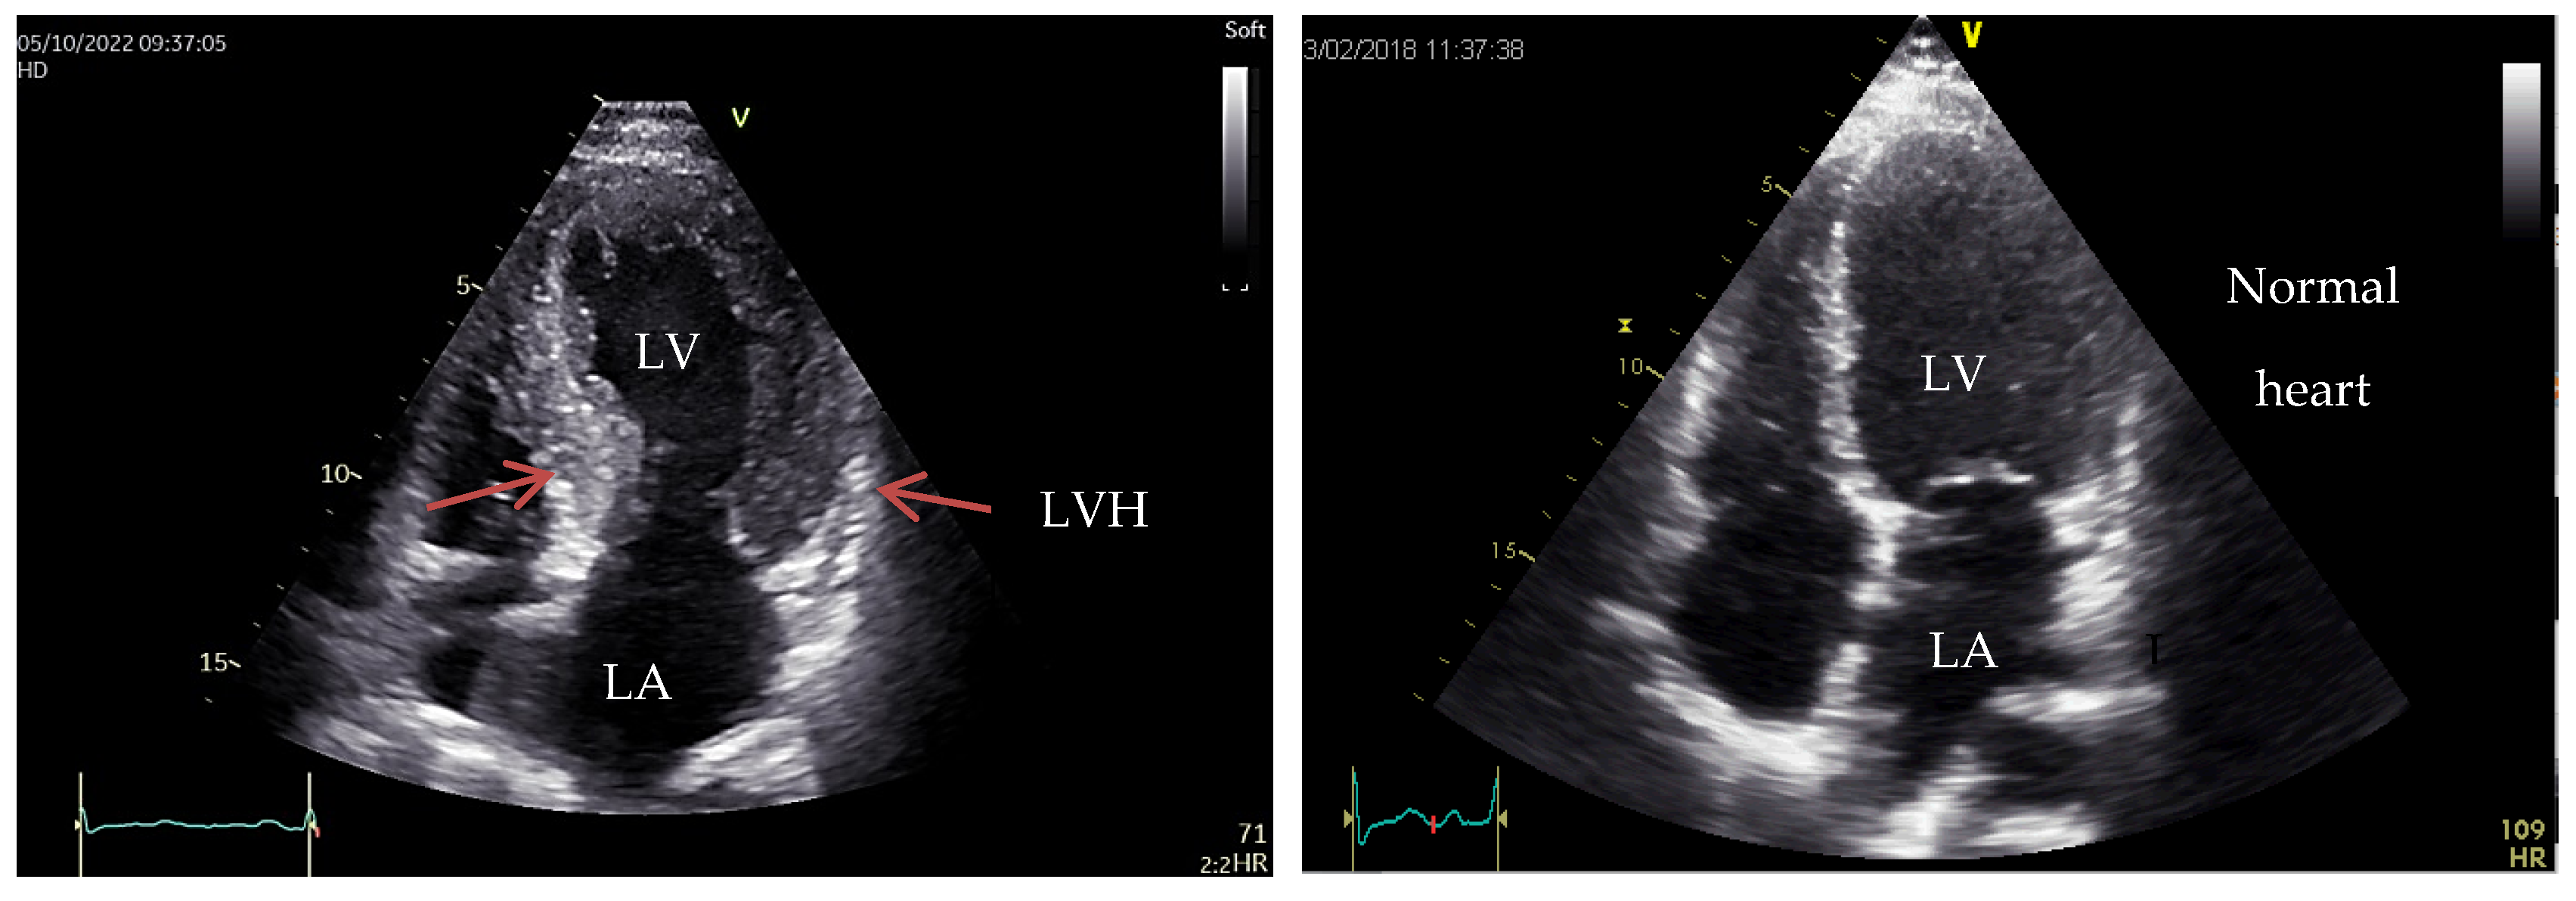

4. Hypertrophic Cardiomyopathy